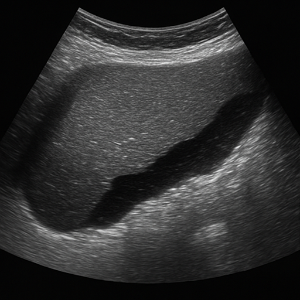

담낭과 담관

담낭은 담석이나 담낭염, 담낭 벽 두께 변화 등을 확인하는 데 아주 유용하답니다. 담관의 확장이나 폐쇄 여부도 복부초음파로 간접적으로 알아볼 수 있어요.

담석증과 담낭염

- 담석증

담낭 안에 작은 돌이 생긴 거예요. 초음파에는 그림자처럼 뚜렷하게 나타나서 찾기 쉬워요. - 담낭염

담낭에 염증이 생기는 것으로, 두꺼워진 벽이나 주변에 생긴 변화가 화면에 보여요.